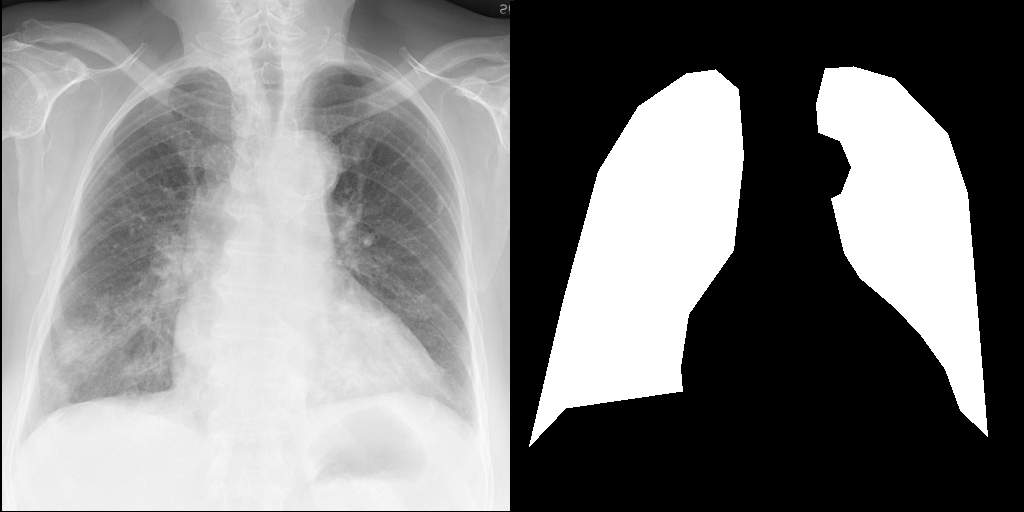

Let's load an example image of a patient with influenza.

import requests

from PIL import Image, ImageDraw

from torchvision import transforms

def download_sample_image() -> Image.Image:

"""Download chest X-ray with CC license."""

base_url = "https://upload.wikimedia.org/wikipedia/commons"

image_url = f"{base_url}/2/20/Chest_X-ray_in_influenza_and_Haemophilus_influenzae.jpg"

headers = {"User-Agent": "RadEdit"}

response = requests.get(image_url, headers=headers, stream=True)

return Image.open(response.raw)

image = download_sample_image()

input_image = transforms.Compose([transforms.Resize(512), transforms.CenterCrop(512)])(image)

right_lung_coords = [(19, 445), (53, 299), (88, 170), (128, 105), (176, 72), (205, 68), (228, 88), (233, 155), (223, 249), (178, 313), (170, 366), (172, 390), (55, 407)]

left_lung_coords = [(477, 435), (466, 298), (457, 192), (437, 132), (384, 77), (343, 65), (315, 67), (306, 102), (308, 131), (330, 140), (341, 166), (331, 192), (321, 197), (334, 252), (350, 277), (383, 305), (410, 333), (435, 368), (450, 409)]

# Create a blank image with the same size as the original image

lung_mask = Image.new("L", (512, 512), 0)

# Draw the filled shape using the coordinates

draw = ImageDraw.Draw(lung_mask)

draw.polygon(right_lung_coords, fill=255)

draw.polygon(left_lung_coords, fill=255)

For this example, we will remove the visual appearance of influence from the lungs, while preventing changes from happening to the rest of the image. To do this, we create a mask of the lung regions and use this as the edit_mask which defines the region we wish the editing prompt to be applied to. Since we want the rest of the image to remain unchanged, we use the inverse as the keep_mask which defines the region where edits are discouraged from taking place.

from PIL import ImageOps

edit_mask = lung_mask

keep_mask = ImageOps.invert(lung_mask)

torch.manual_seed(1234)

prompt = 'No acute cardiopulmonary process'

edited = radedit_pipeline(

prompt,

weights=[7.5],

image=input_image,

edit_mask=edit_mask,

keep_mask=keep_mask,

num_inference_steps=200,

invert_prompt='',

skip_ratio=0.3,

output_type="pil",

)